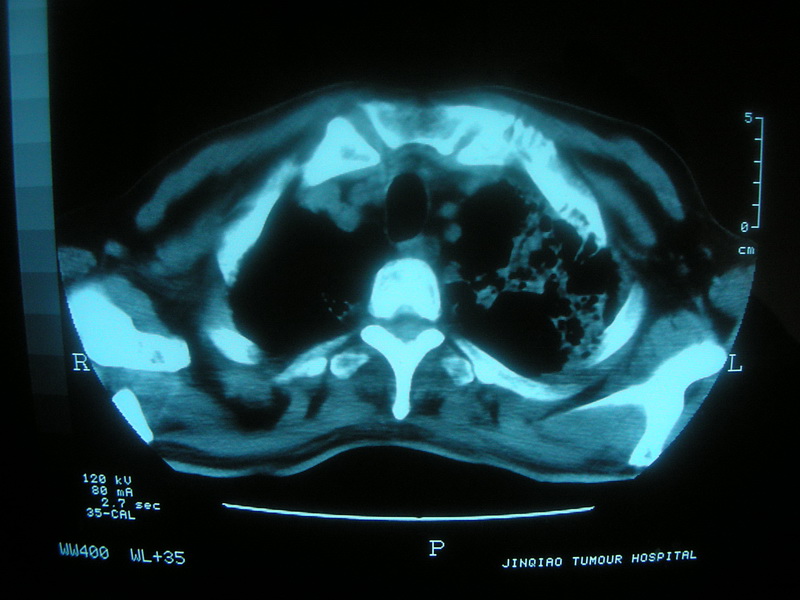

标题: CT11692:男,63岁,糖尿病史15年.抗炎治疗7天,病情 [打印本页]

标题: CT11692:男,63岁,糖尿病史15年.抗炎治疗7天,病情

请老师看看是结核还是炎症?